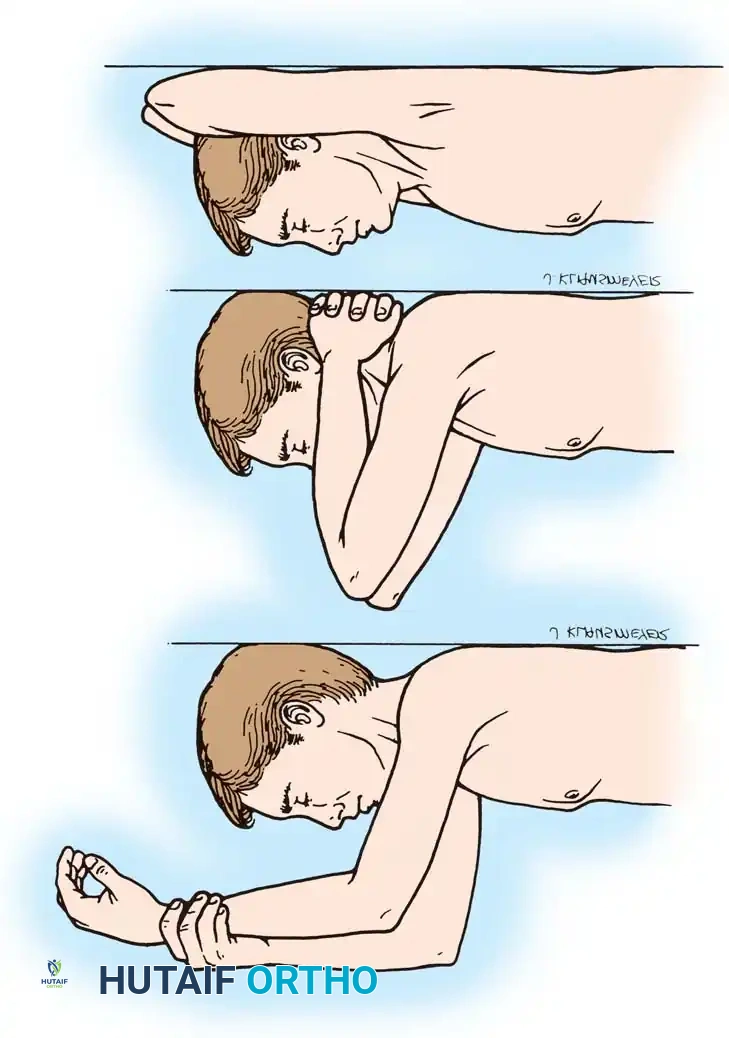

- Triceps Management: Several options exist, including a triceps-reflecting approach (Bryan-Morrey), a triceps-splitting approach, or a triceps-sparing approach. The Bryan-Morrey approach involves reflecting the triceps from medial to lateral in continuity with the anconeus and forearm fascia.

4. Closure

The triceps mechanism is meticulously repaired using heavy non-absorbable sutures through drill holes in the proximal ulna. The ulnar nerve is secured in a subcutaneous anterior transposed position, ensuring no fascial bands compress it.

- Days 1-3: The arm is immobilized in extension in a bulky Jones dressing to minimize swelling and protect the wound.

- Weeks 1-6: The dressing is removed, and a hinged elbow brace is applied. Active and active-assisted ROM is initiated. Triceps strengthening is strictly avoided for 6 weeks to protect the extensor mechanism repair.